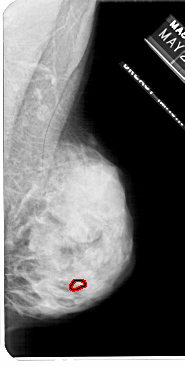

RIGHT_MLO LINES 5491 PIXELS_PER_LINE 2761 BITS_PER_PIXEL 12 RESOLUTION 43.5 OVERLAY

FILE: A_1113_1.RIGHT_MLO.OVERLAY

TOTAL_ABNORMALITIES 1

ABNORMALITY 1

LESION_TYPE CALCIFICATION TYPE PLEOMORPHIC DISTRIBUTION CLUSTERED

ASSESSMENT 4

SUBTLETY 3

PATHOLOGY MALIGNANT

TOTAL_OUTLINES 1

BOUNDARY